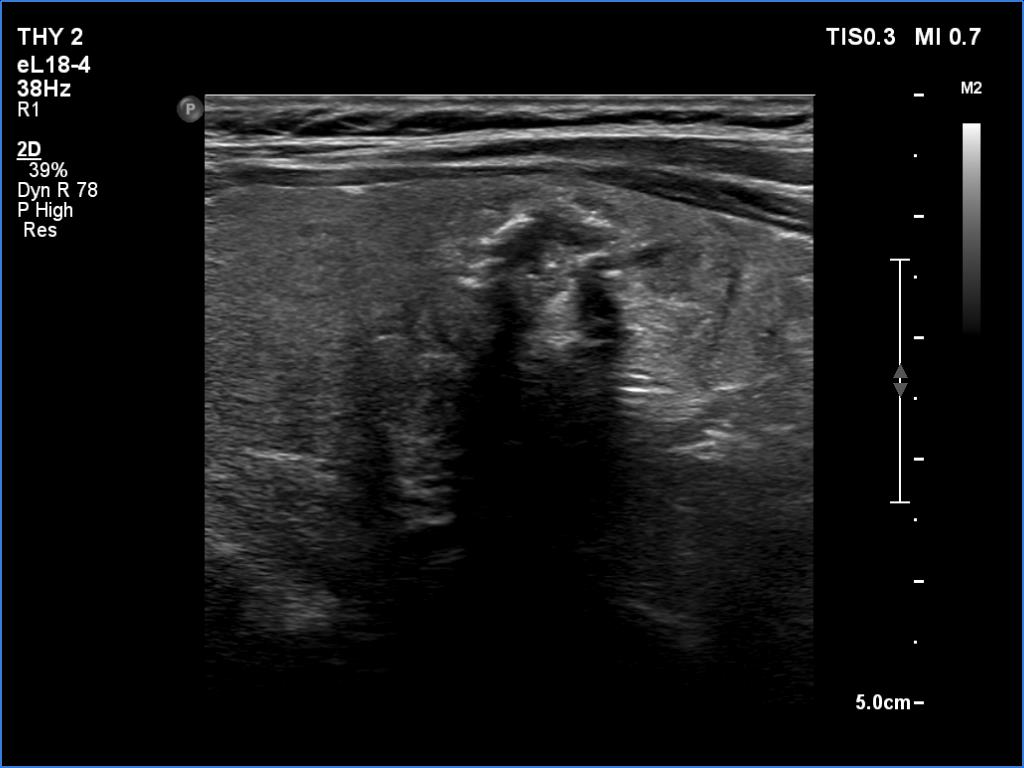

Ultrasonography. There was an irregular, large hypoechoic mass in the right lobe. The nodule has irregular, lobulated margins and was hard on elastography. A much smaller, similar nodule was in the lower-medial part of the left lobe.